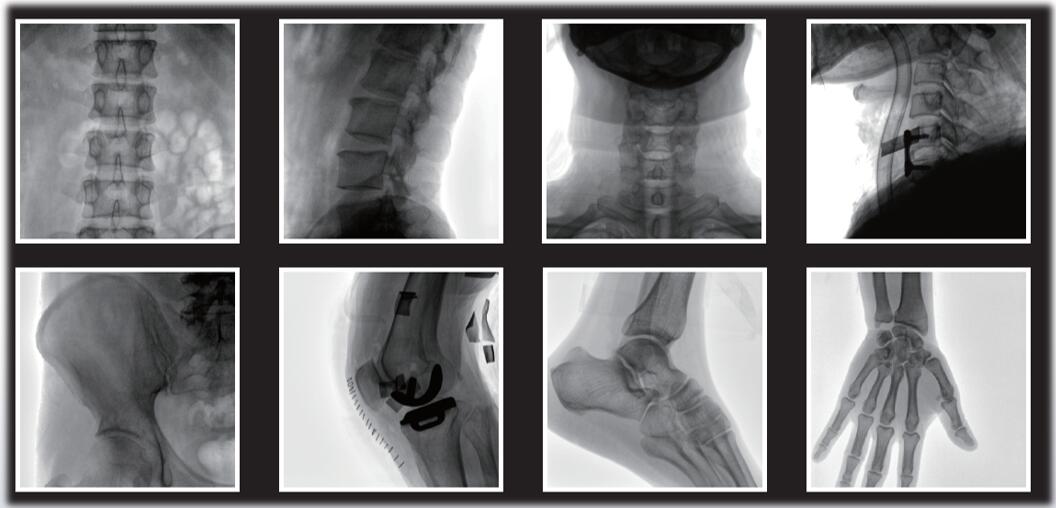

大尺寸動態平板探測器,圖像清晰細膩,滿足臨床多種檢查。

采用了多分辨率圖像增強處理技術,不同部位不同圖像處理。

平板小C臂在骨科手術中的定位、診斷、微創手術的開展與治療中發揮獨特的作用。作為一名醫生,您需要清晰的圖像質量來幫助您應對更具挑戰性的介入治療。PLX118系列平板小C臂為您提供優良的圖像、靈活的操作體驗和更低的劑量表現。如果您想采購,或了解產品具體參數,歡迎咨詢400-025-6366。